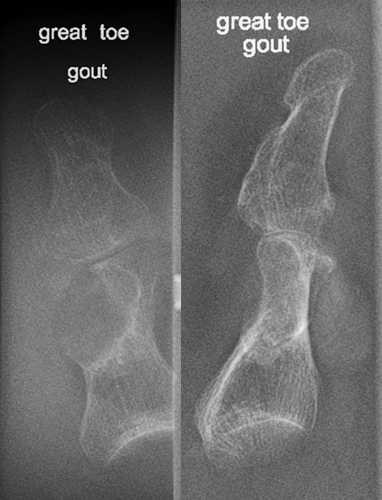

Common site for gout?

First MTP joint of the big toe.

Radiographic signs of gout?

Late changes: “mouse-bitten” erosions, overhanging edges, possible calcified tophi; no osteopenia.